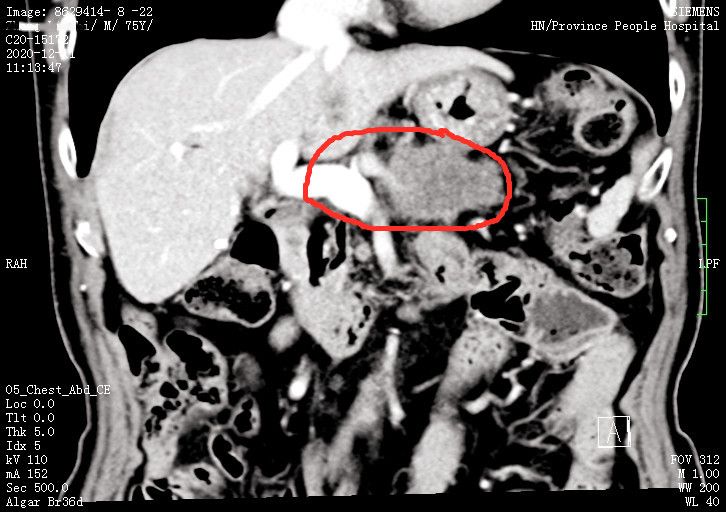

75岁的张先生在海南工作多年后退休,2020年8月体检发现肿瘤标志物增高,经检查发现“胰腺体尾部肿瘤”。肿瘤不仅侵犯了门静脉、肠系膜上静脉等重要血管,还累及胃后壁、空肠桥袢等脏器;加上患者19年前因为胆总管及胆囊结石、十二指肠憩室做过腹部大手术,在当地多家医院就诊,得到的答复都是“手术难度和风险极大”。在当地医院的建议下,张先生于2020年12月9日来到湖南省人民医院肝胆医院就诊,并住进胰脾外科病房。

胰脾外科主任成伟教授邀请首席专家吴金术教授及肝胆医院院长陈梅福教授多次会诊,他们一致认为手术具有很大难度:患者75岁高龄,曾经做过胆囊切除、胆道探查、胆总管十二指肠吻合、胃大部分切除、胃空肠吻合术,解剖结构紊乱,术中粘连也会很严重;胃肠吻合口及结肠中动脉横跨在肿瘤前方,手术操作空间狭小,要在胃左动脉和十二指肠形成的狭缝中“抽丝剥茧”游离受累血管,并进行血管切除和吻合;门静脉、肠系膜上静脉、肠系膜上动脉、脾静脉、脾动脉、胃左动脉等多支重要血管都被肿瘤侵犯;空肠和胃受累,加上患者上次手术切除大部分胃以后,只剩下胃左动脉一条胃供血动脉。因此,此次手术既要切除胃部病灶,又不能损伤胃左动脉,否则患者的胃将不保。

经过认真讨论并制定周密的手术方案,吴金术教授、陈梅福教授、成伟教授、肖鹏飞医师组成的手术团队,成功为患者切除一个约5厘米×6厘米、网球大小的胰腺肿瘤,并给予肠粘连松解、胃部分切除、胃空肠吻合重建、肠系膜上静脉门静脉楔形切除重建、胰腺肿物活检、胰体尾切除、脾切除、左肾上腺部分切除+淋巴结活检、胃造瘘、十二指肠造瘘、空肠造瘘。